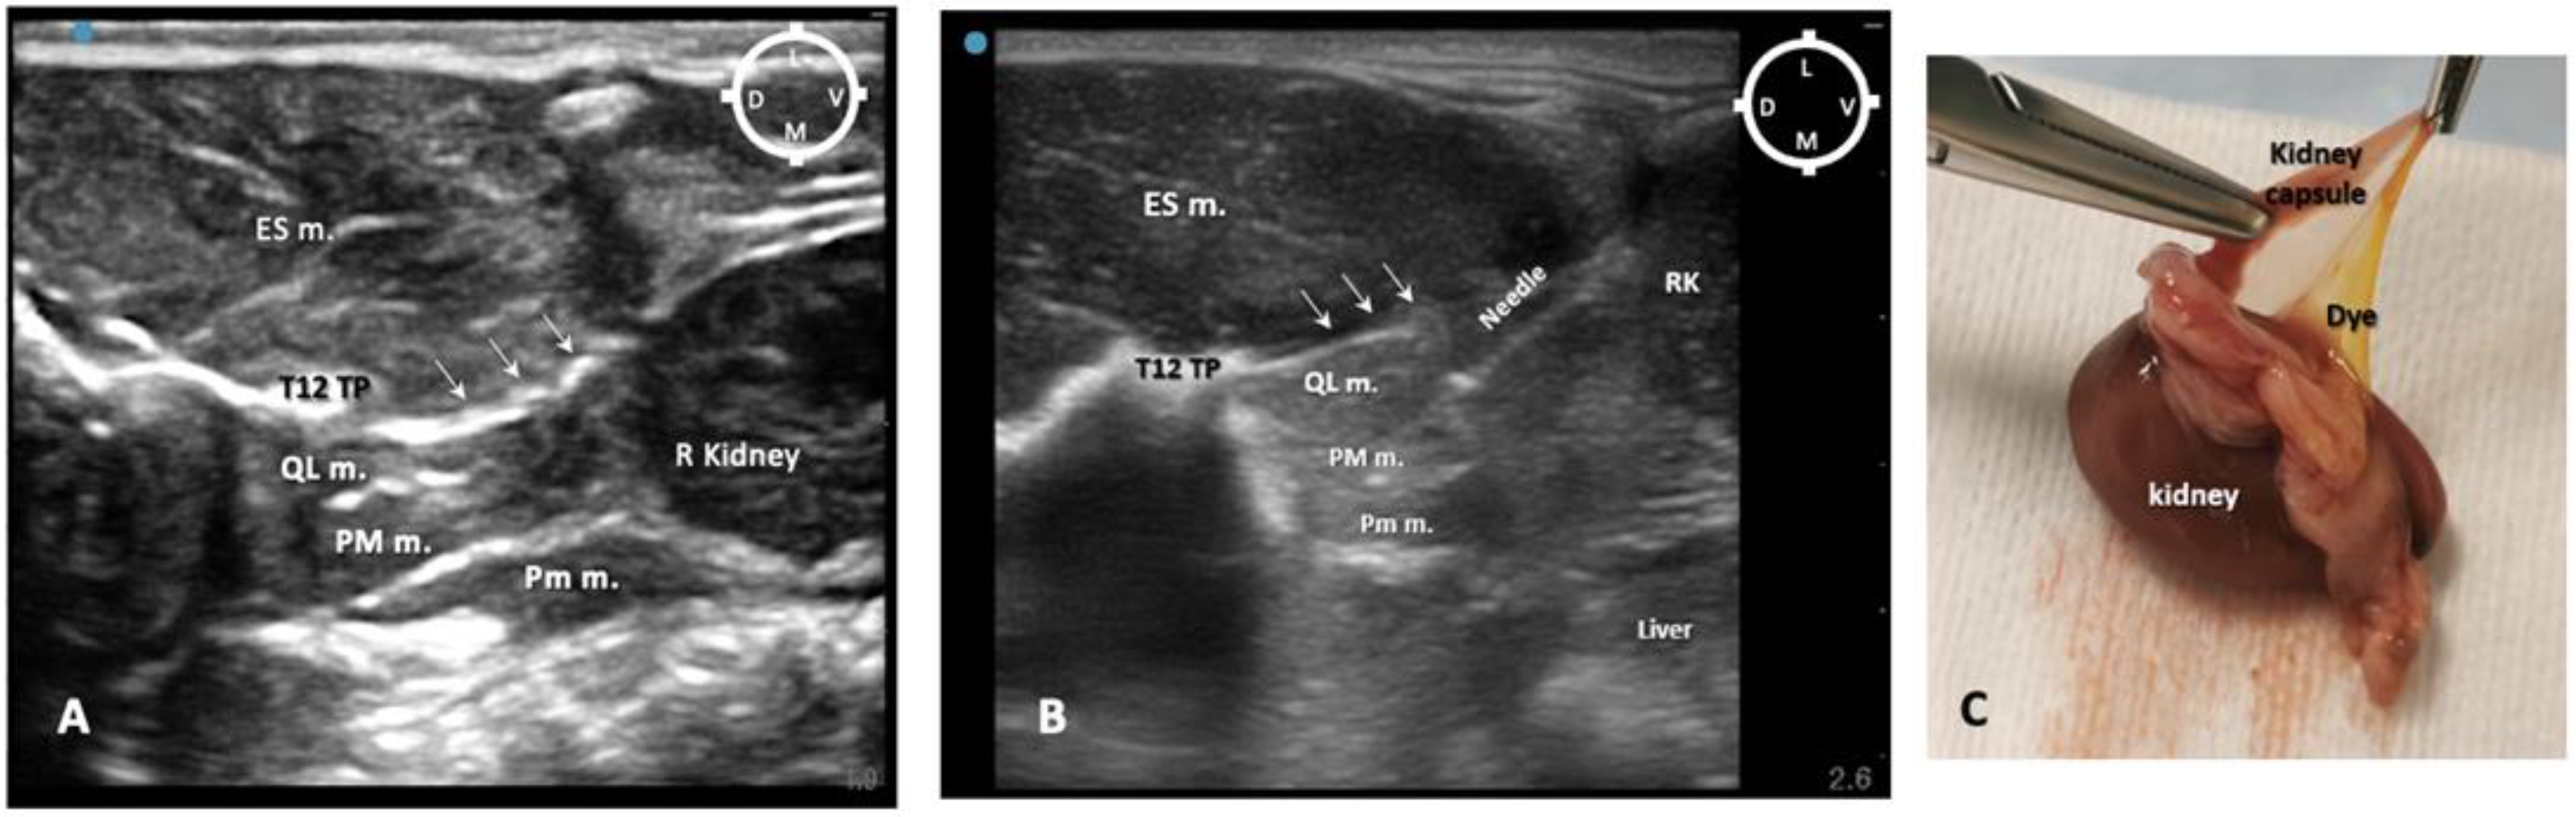

Figure 3. Sono-anatomy of the thoracolumbar area at the level of the twelfth thoracic vertebra transverse process (T12 TP). The arrows point out the thoraco-lumbar (TL) fascia (dot line). The quadratus lumborum muscle (QL m.) is located ventral to the transverse process and the TL fascia and dorsal to the psoas major muscle (PM m.). The injection point for the ultrasound-guided quadratus lumborum block is within the quadratus lumborum fascia the hyperechoic line separating the PM m. and the QL m (yellow dot line). AV abdominal viscera; D dorsal; ES m. erector spinae muscles; L lateral; M medial; Pm m. psoas minor muscle; V ventral; T12 TP Transverse process of the twelfth thoracic vertebra. Cyan blue dot represents the probe marker pointed in this case dorsally.

To overcome this complication, on the other two of four rabbits scheduled for the sono-anatomy and quadratus lumborum block design phase, the needling was performed using a modified dorsolateral approach as reported recently in dogs by Viscasillas and colleagues (2021), in which the needle passed through the epaxial muscles and a medial injection site was performed in the quadratus lumborum fascia, between the QL and PM muscles. This avoided visceral contamination with dye solution in these remaining two rabbits. For this reason, in the present study, only the dorsal approach was subsequently used (Figure 3).

In relation to the surrounding structures, the erector spinae muscles (particularly developed in rabbits) were located dorsally to the thoraco-lumbar fascia and the quadratus lumborum muscle, which was located dorsally and medially in relation to the psoas major muscle within the same acoustic window (range of depths between 1 and 2 cm). During the insertion of the needle, the tip and shaft were always visible in 8/10 rabbits (16/20 QLBs). In order to reach the targeted fascia, the needle was passed through the erector spinae muscles, pierced the thoraco-lumbar fascia, passed through the QL muscle and finally reached the target, the quadratus lumborum fascia. This fascia surrounds the QL muscle and separates it from the PM muscle. The mean depth of the targeted area of injection (QL fascia) was recorded as 1.5 ± 0.09 cm amongst all cadavers (Figure 6A,B).